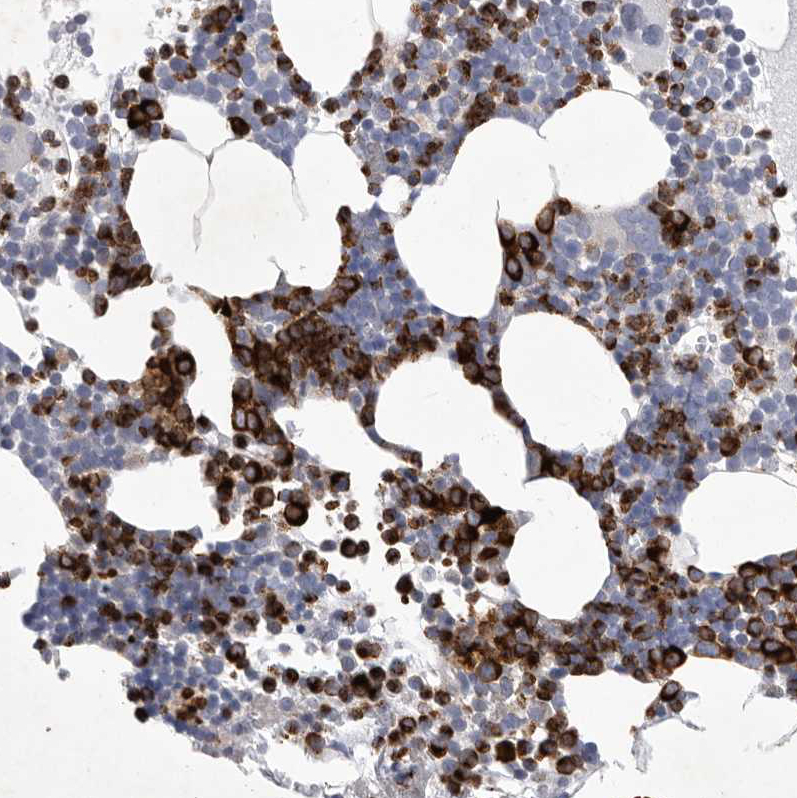

Immunohistochemical staining of human bone marrow shows strong cytoplasmic / membranous positivity in hematopoietic cells.